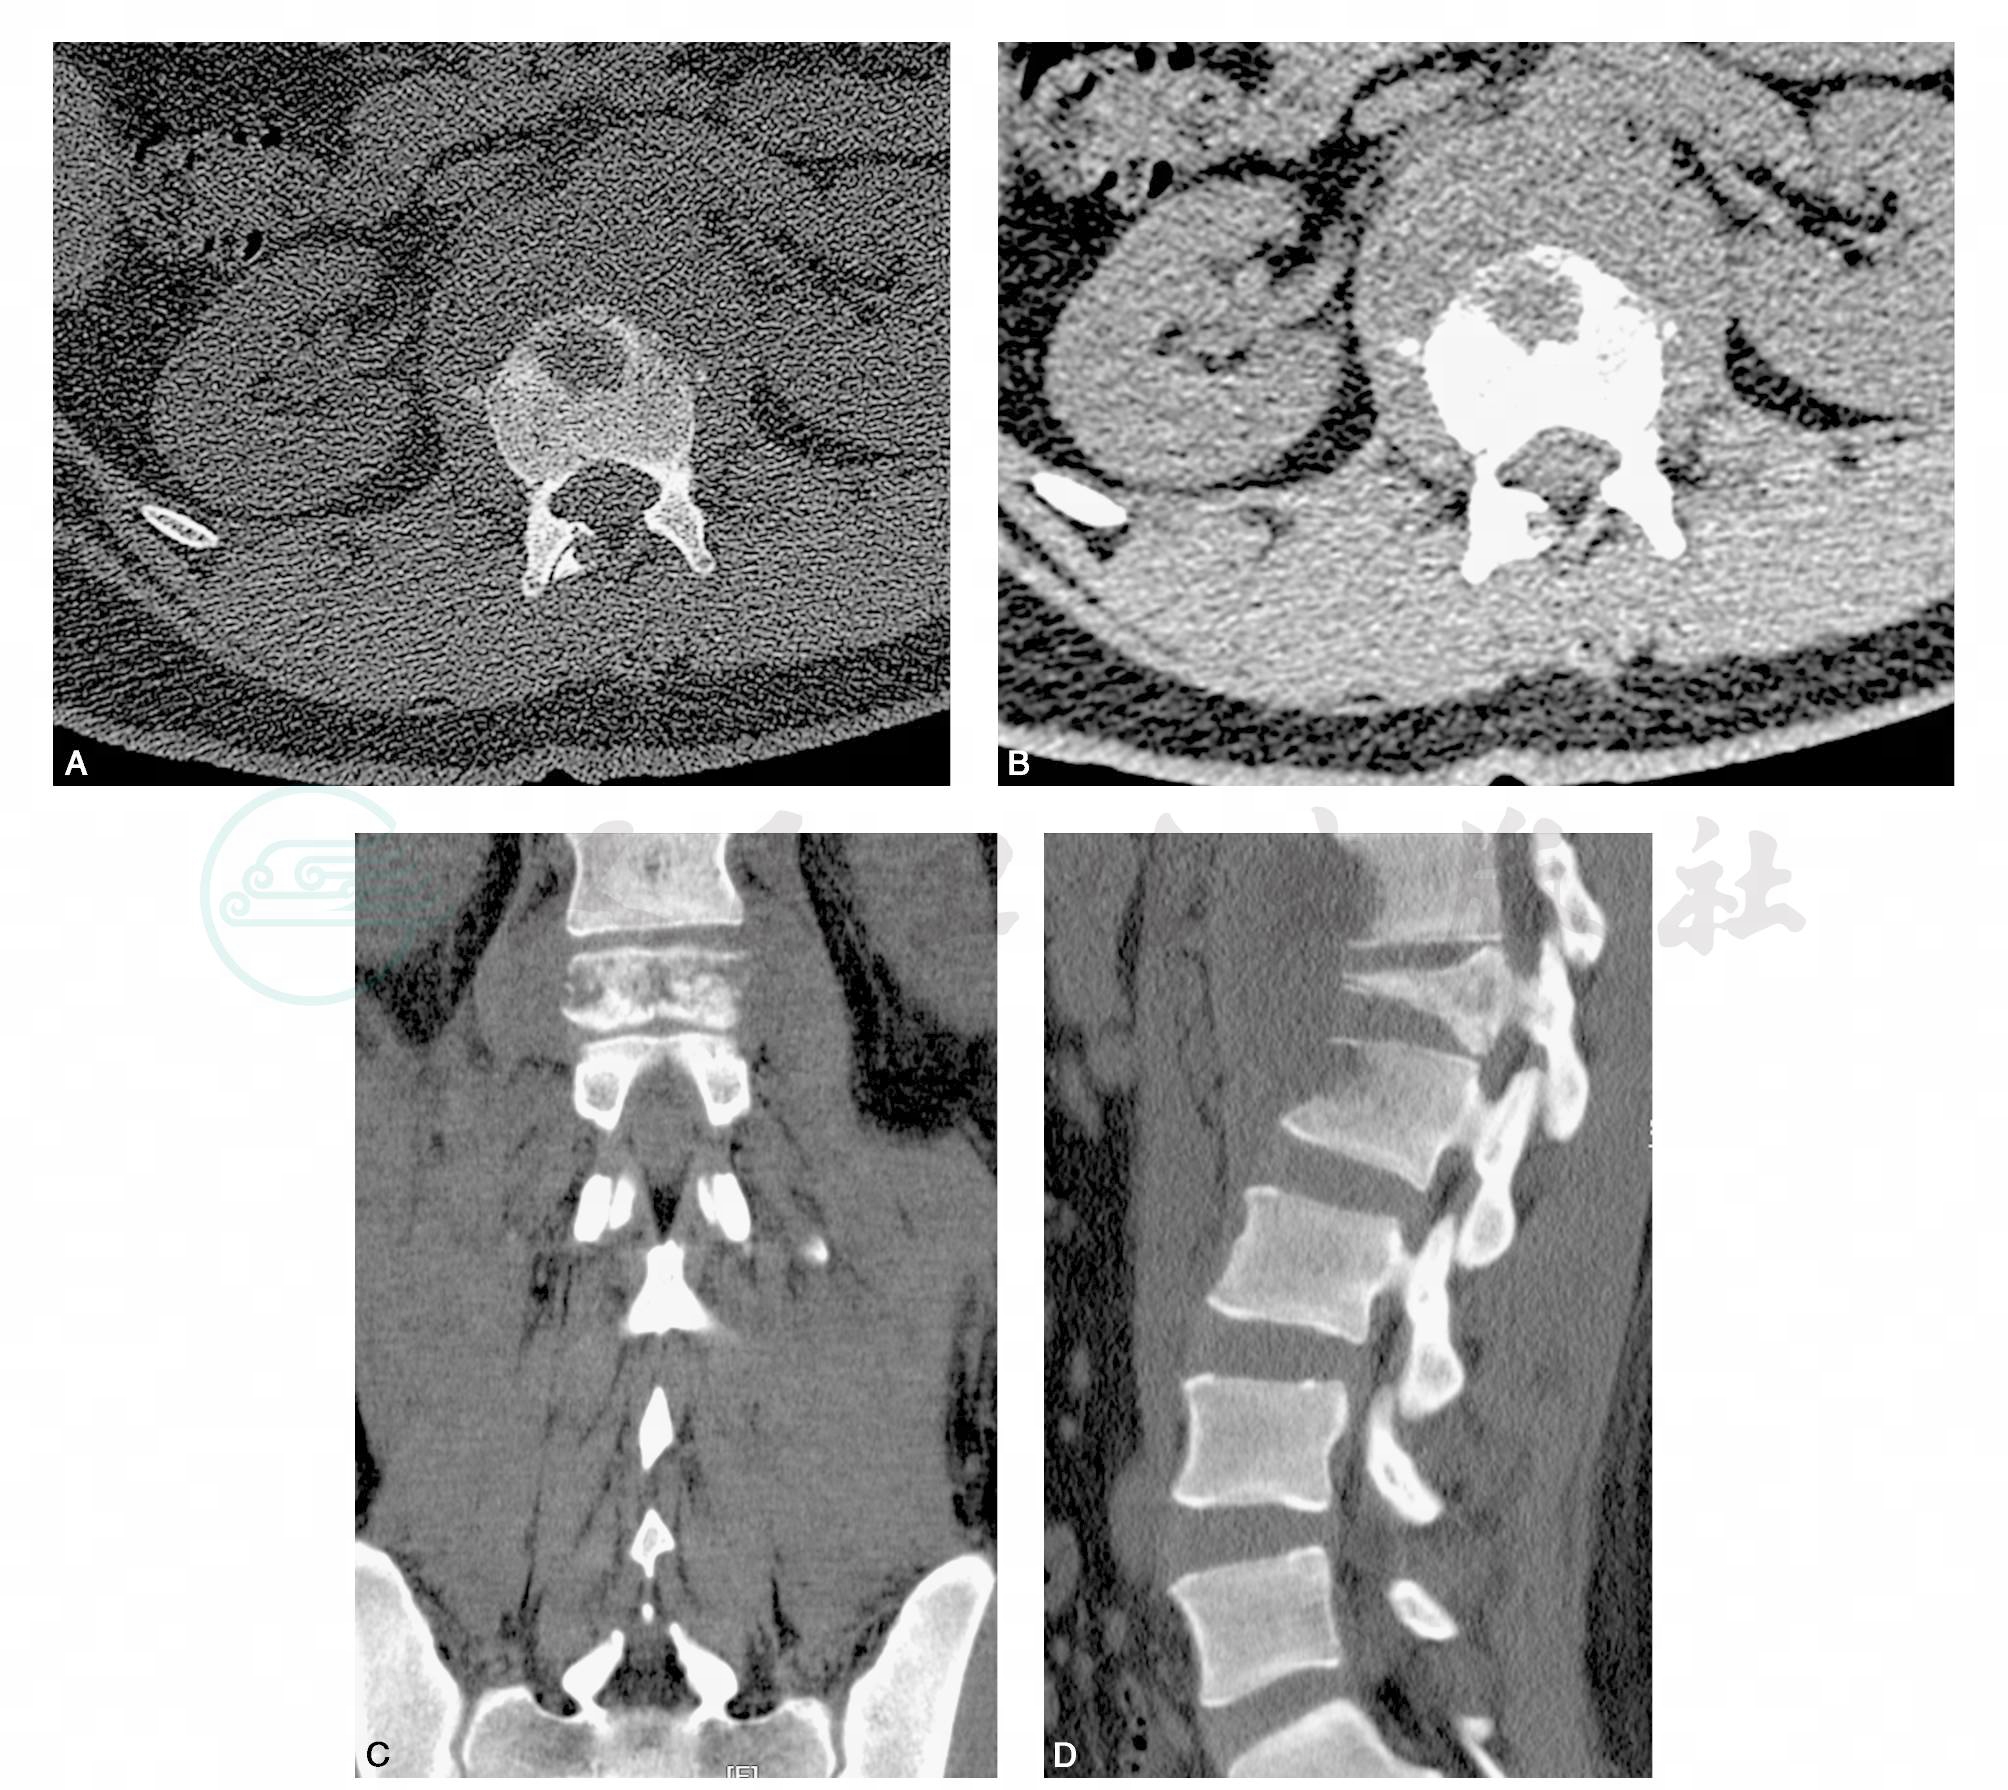

图3 CT:腰1椎体楔形变,周围多发小骨块影,椎体周围可见软组织密度影环绕椎体旁,病灶与双侧腰大肌、双侧膈肌脚分界不清。胸12~腰1、腰1~2椎间隙变窄。腰2椎体前缘可见条状骨性密度影

引自:主编:.疑难病例影像诊断评述.第1版.ISBN:978-7-117-16817-5